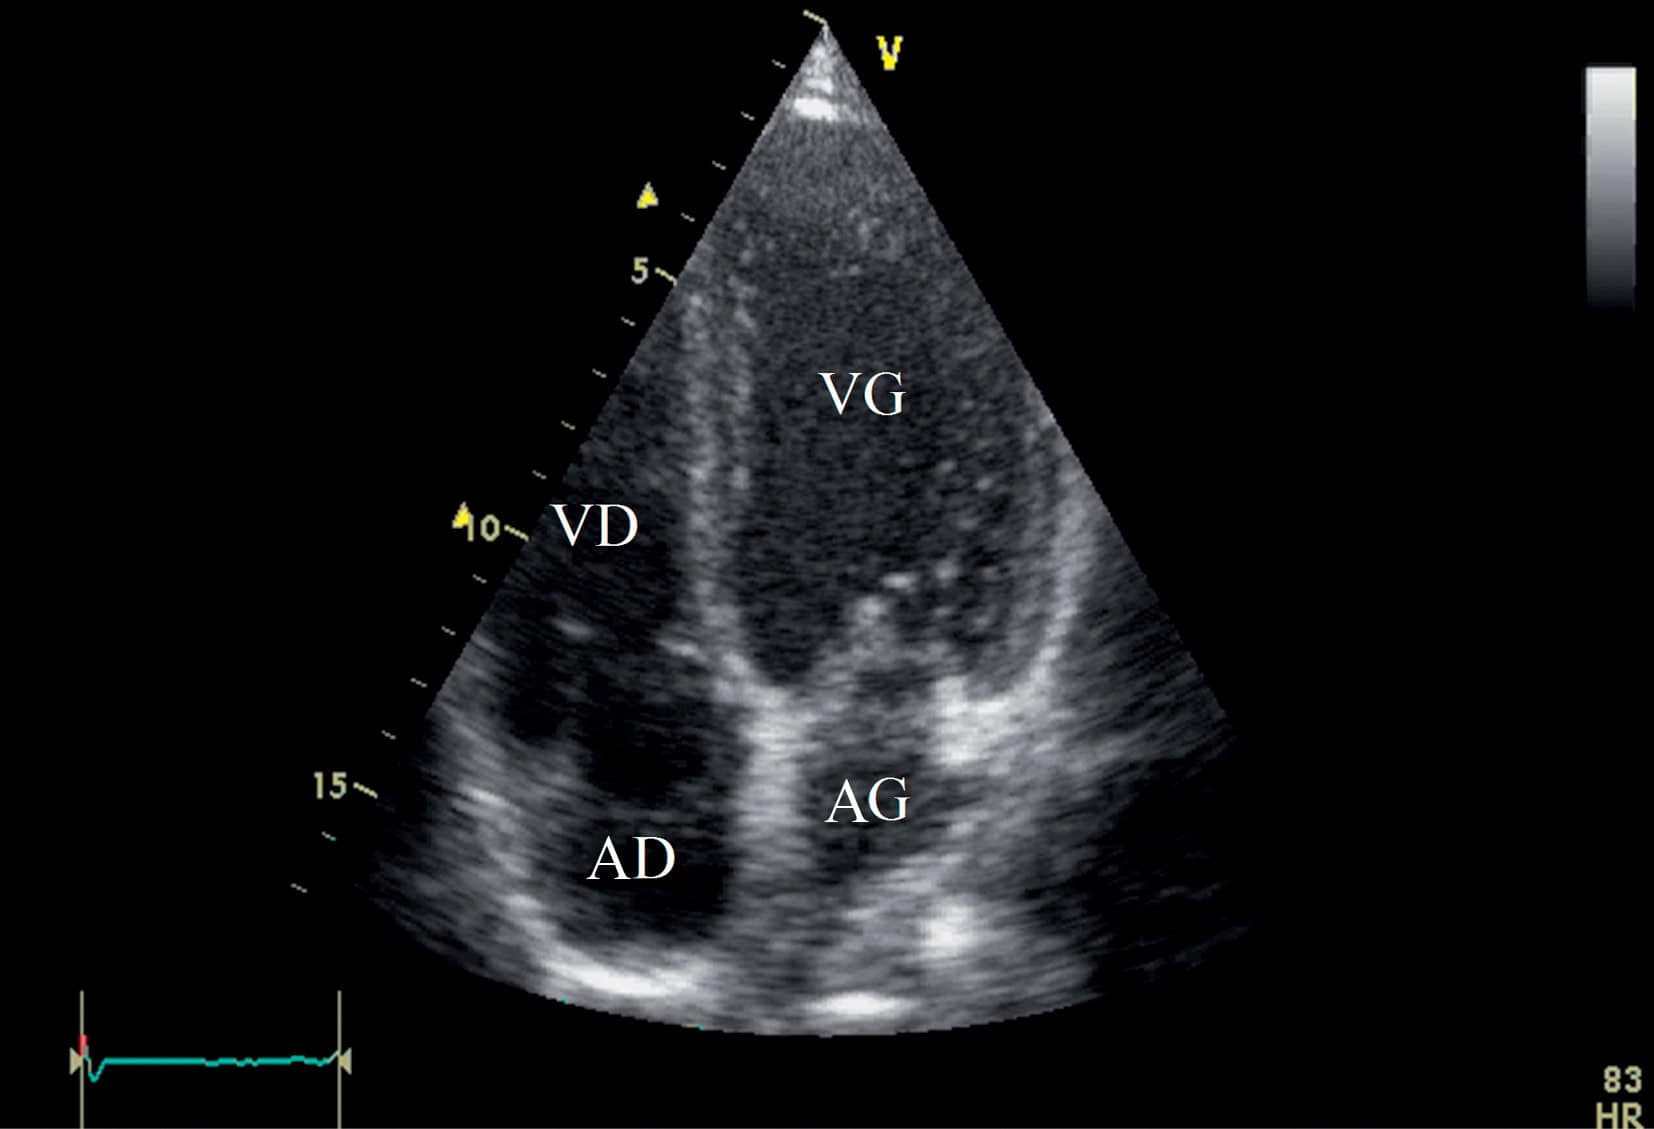

CARDIOLOGIE PÉDIATRIQUE 📌 À LA UNE : Cardiac evaluation of paediatric athletes: A clinical [...]